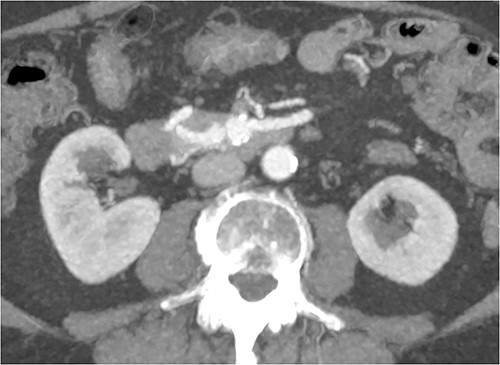

CT of abdomen and pelvis was performed, which revealed a 13 mm indeterminate lesion arising between the pancreatic uncinate process and the duodenum with coarse peripheral calcification, suspicious of primary pancreatic neoplasm or primary small bowel cancer (Figs 2–4).

Initial CT: axial view, demonstrating what was initially thought to represent indeterminate pancreatic/duodenal lesion.